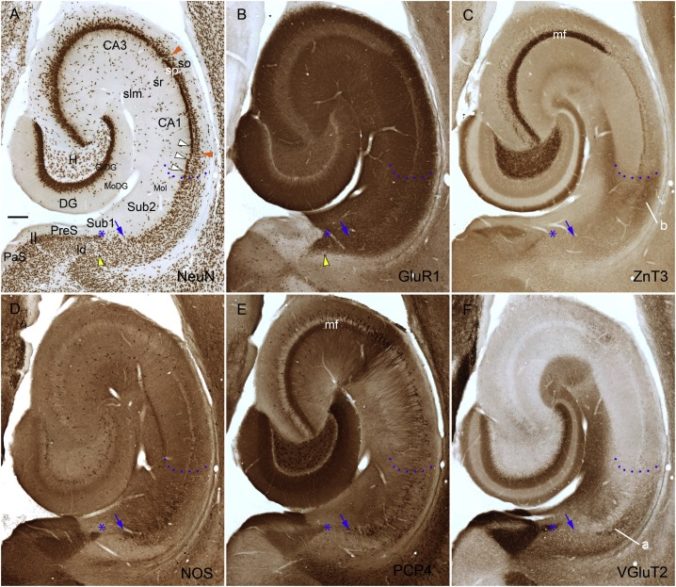

- Foto Archivado el 11 de febrero de 2017 en Wayback Machine.

- Foto